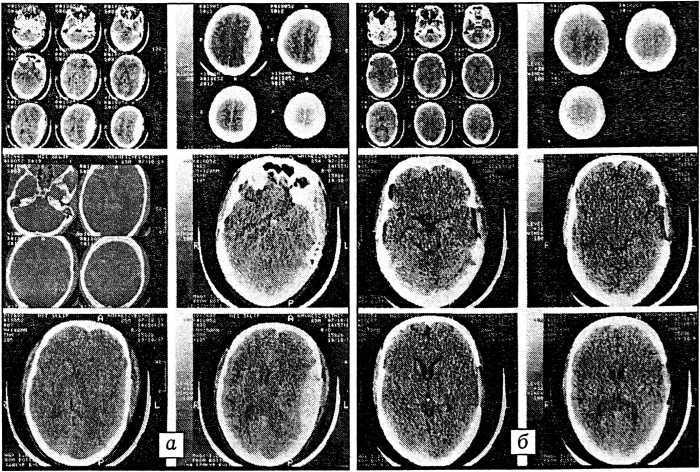

После выведения больного из шока выполнена компьютерная томография черепа. Выявлены вдавленный перелом левой височной кости и линейный перелом большого крыла клиновидной кости слева, эпидуральная гематома (100 см3) в левой лобно-височно-теменной области с дислокацией срединных структур (7 мм вправо) и сдавлением стволовых структур; ушибы мозга I типа в левой лобной и височных долях; отек мозга (рис. 4, а).

Рис. 4. Компьютерные томограммы черепа больного М. а — перелом свода и основания черепа; субдуральная и эпидуральная гематомы; б — после операции.

Через 6 ч 45 мин после поступления пострадавшего по витальным показаниям произведена под наркозом операция: краниотомия слева, удаление эпидуральной (100 мл) и субдуральной (5 мл) гематом (рис. 4, б). Послеоперационное течение гладкое. На 2-е сутки после травмы сознание восстановилось до уровня сопора. Гемодинамика стабилизировалась, тяжесть ЧМТ по шкале Глазго — 7 баллов. Под наркозом произведен интрамедуллярный остеосинтез бедренной кости массивным металлическим штифтом и шурупом (рис. 3, б). Операция длилась 50 мин и прошла без осложнений. Послеоперационные раны зажили первичным натяжением.